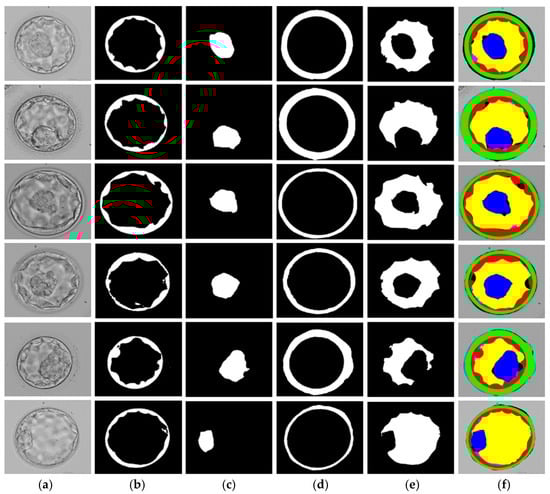

3.3. Evaluation of the Proposed PSF-Net

| ICM | BL | TE | ZP |

|---|---|---|---|

| 1.47 | 1.73 | 1.43 | 1.35 |

| 1.52 | 1.70 | 1.39 | 1.40 |

| 1.46 | 1.61 | 1.48 | 1.52 |

| 1.46 | 1.68 | 1.43 | 1.38 |

| 1.39 | 1.61 | 1.49 | 1.58 |